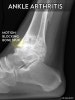

X-ray : 발목 관절염(Ankle arthritis)

관절 연골은 소실, 관절연골은 협소화되고 연골하골의 경화, 낭포 형성이나 관절 주위의 골극 형성이 나타납니다.

측면에서는 거골 활차는 편평화, 정면에서는 둥그스름하게 되어, 내외과의 각도는 벌어집니다.